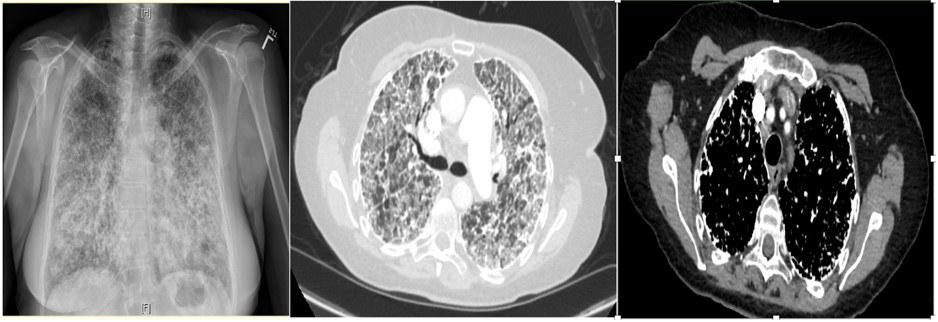

A 65-year-old non-smoking Caucasian female presented with 2-years of progressively worsening dyspnea and dry cough. She denied any history of malignancy, sick contacts, pets, or significant exposures. On physical examination, she was noted to have scattered crackles. Sputum culture and viral respiratory panel were negative, and autoimmune serology workup, including ANA, RF, MPO, PR-3, Anti-CCP, C-ANCA, P-ANCA, and anti-Scl-70, were within normal limits. Chest x ray, CT chest revealed the below findings (Figure 1):